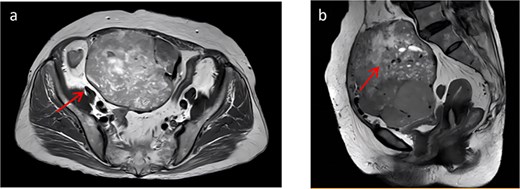

At presentation, contrast-enhanced computed tomography (CT) demonstrated a multiloculated mixed cystic–solid mass in the lower abdomen/pelvis with internal septations, measuring ~13.2 × 9.5 × 12.4 cm (Fig. 1). The lesion was well outlined overall but showed indistinct planes with the adjacent bowel and the anterior bladder wall. Enhancement was heterogeneous, with multiple non-enhancing low-density foci consistent with necrosis. Arterial feeders arose from both external iliac arteries. Magnetic resonance imaging (MRI) confirmed a predominantly solid, lobulated mass (12.3 × 9.6 × 13.7 cm; Fig. 2) with heterogeneous signal (T1 isointense; variable T2 signal) and mildly increased diffusion signal; the minimum ADC was ~0.6 × 10−3 mm2/s. Small cystic/necrotic areas were present, and the tumor appeared locally adherent to the bowel and bladder, favoring a mesenchymal neoplasm.

(a) Shows a cross-sectional view of pelvic contrast-enhanced MRI. (b) Shows a sagittal view of pelvic contrast-enhanced MRI.